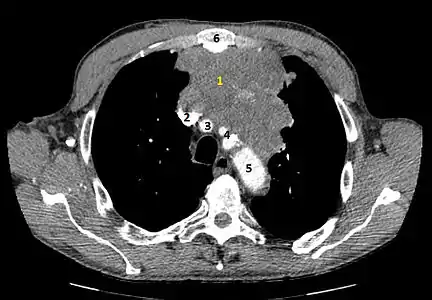

- Aspect scannographique

Présentation tomodensitométrique classique d'un thymome à un stade précoce (cercle rouge). À l'arrière, l'aorte, la veine cave supérieure et l'artère pulmonaire sont visibles en coupe.

Scanner injecté, en fenêtre médiastinale, montrant un carcinome thymique envahissant les structures médiastinales :

1 : tumeur hétérogène, aux contours irréguliers, présentant des plages hémorragiques ;

2 : veine cave supérieure ;

3 : tronc artériel brachiocéphalique ;

4 : artères sous-clavière gauche et carotide commune gauche ;

5 : crosse de l'aorte ;

6 : sternum.